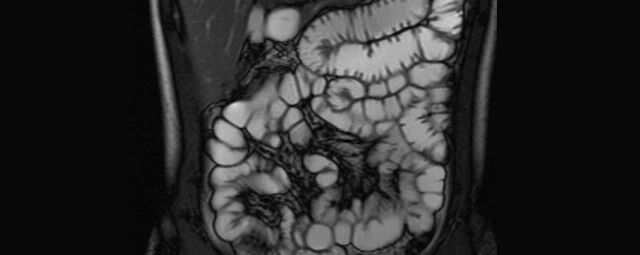

Abdomen/Becken

• Leber

• Beurteilung von Lebervergrößerung und Leberverfettung

Abgrenzung gutartiger (z.B. Hämangiom, FNH oder Zysten) von bösartigen Lebererkrankungen (z.B. hepatozelluläres Karzinom, Metastasenverdacht)

• exakte Zuordnung krankhafter Prozesse zu einzelnen Lebersegmenten vor einer geplanten Operation.

• Therapieverlaufskontrolle

• Gallenwegssystem

• Nichtinvasive Darstellung der Gallenwege (MRCP)

• Abklärung der Ursache einer Gallenabflussbehinderung (Tumor, Gallensteine, Entzündung)

• Pankreas

• Diagnostik des Pankreaskarzinoms und Pankreasentzündung

• weitere Einordnung von Pankreaszysten (z.B. Pseudozysten, IPMN)

• Nieren

• Abklärung der Ursache einer Harnstauung (MR-Urographie)

• Abgrenzung gutartiger (z.B. Zysten) von bösartigen Nierenerkrankungen (Nierenzellkarzinom)

• Auffälligkeiten an Nebennieren (z.B. Adenom, Karzinom)

• Darm

• Darstellung bzw. Kontrolle im Verlauf bei perianalen Fisteln und Abszessen

• Verlaufskontrolle des Lokalbefundes nach Rektumentfernung bei Karzinom